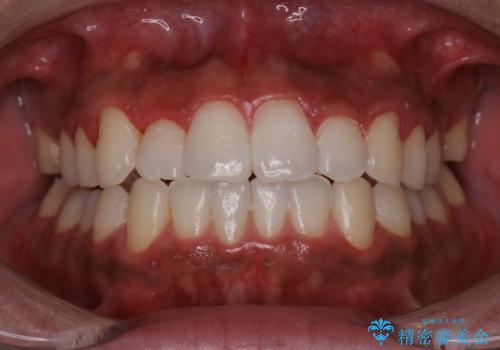

- 忙しくて、しばらくクリーニングをしていないため、全体的にしっかりとクリーニングしてほしいとのことでした。PMTC60分コースを行いました。

PMTCは審美的な面だけではなく、虫歯や歯周病予防にもなります。虫歯や歯周病予防のためには、お口の中を清潔に保つことが大切です。